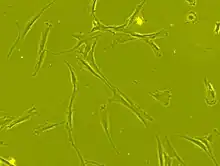

Mesenchymal stem cells (MSCs), a term first named by Arnold I. Caplan in 1991,[5] are characterized morphologically by a small cell body with a few cell processes that are long and thin. While the terms mesenchymal stem cell (MSC) and marrow stromal cell have been used interchangeably for many years, neither term is sufficiently descriptive:

Morphology

The cell body contains a large, round nucleus with a prominent nucleolus, which is surrounded by finely dispersed chromatin particles, giving the nucleus a clear appearance. The remainder of the cell body contains a small amount of Golgi apparatus, rough endoplasmic reticulum, mitochondria, and polyribosomes. The cells, which are long and thin, are widely dispersed, and the adjacent extracellular matrix is populated by a few reticular fibrils, but is devoid of the other types of collagen fibrils.[11][12] These distinctive morphological features of mesenchymal stem cells can be visualized label-free using live cell imaging.

The International Society for Cellular Therapy (ISCT) has proposed a set of standards to define MSCs. A cell can be classified as an MSC if it shows plastic adherent properties under normal culture conditions and has a fibroblast-like morphology. In fact, some argue that MSCs and fibroblasts are functionally identical.[13] The study in Science, "Multilineage Potential of Adult Mesenchymal Stem Cells," describe how MSCs can undergo osteogenic, adipogenic and chondrogenic differentiation ex vivo. As of November 2023, this paper has been cited over 29,000 times. The cultured MSCs also express on their surface CD73, CD90 and CD105, while lacking the expression of CD11b, CD14, CD19, CD34, CD45, CD79a and HLA-DR surface markers.[14]